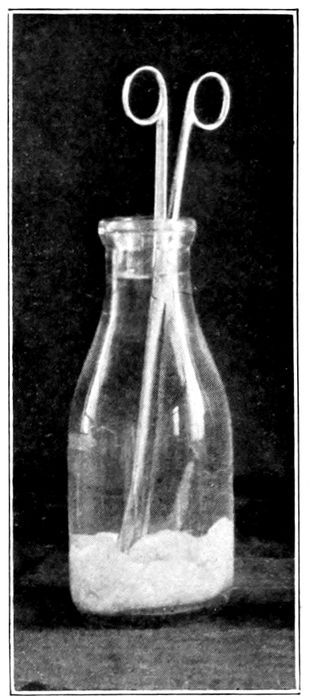

| 52. |

Handling forceps, kept sterile in a jar of alcohol |

132 |